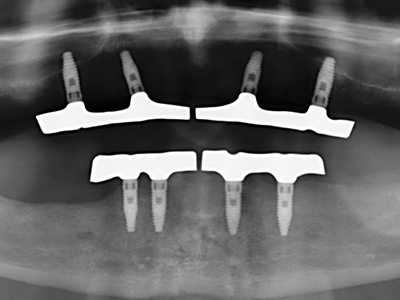

Special soft tips for peri-implantitis therapy are opening up new prospects in dentistry. They are the subject of current research and initial results are very promising.